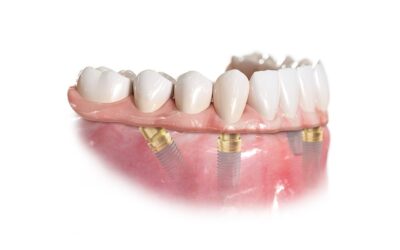

在牙床上植入少數幾根植體 再將活動假牙固定在植體套件上 穩定性佳、咬合力強、不易脫落 適合全口缺牙者 想改善傳統假牙鬆脫問題 保有拆卸清潔的方便性 治療症狀:全口缺牙、傳統活動假牙鬆脫 適用對象:想提升假牙穩定性|希望可拆卸清潔者...